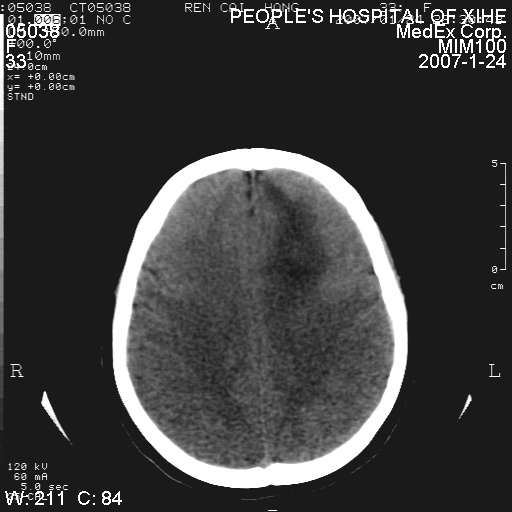

以下是引用卜一在2007-1-25 6:40:00的发言:[br]左侧额叶囊实混杂性病灶,多考虑胶质细胞瘤(ⅱ-ⅲ级),建议增强检查。[br]支持!

以下是引用wwwwtyy在2007-1-25 0:27:00的发言:[br]胶质瘤可能性大,不除外脑白质病变,建议强化

以下是引用xclzq_910在2007-1-25 12:41:00的发言:[br]左额叶条片状低密度灶,考虑占位,建议增强

以下是引用守望可可西里在2007-1-25 0:13:00的发言:[br]左侧额叶囊实混杂性病灶,多考虑胶质细胞瘤(ⅱ-ⅲ级),建议增强检查!